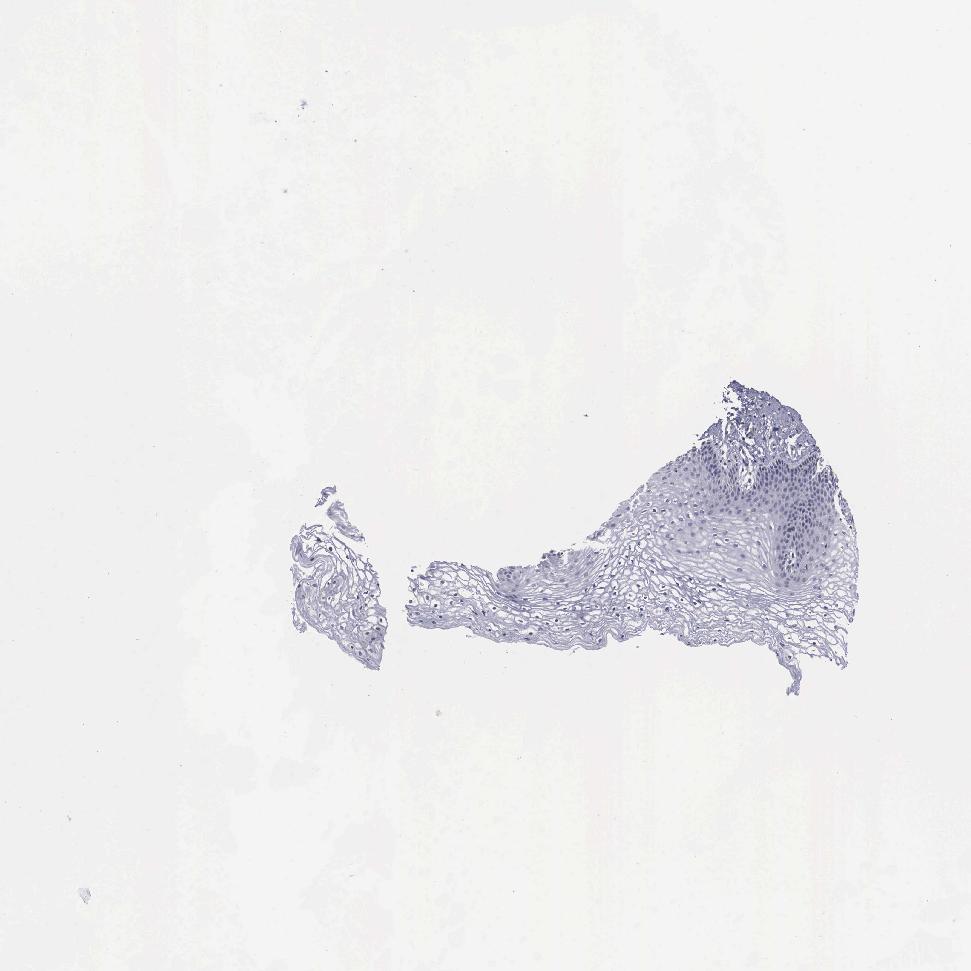

VAGINA - Antibody stainingi

Antibody staining in the annotated cell types in the current human tissue is reported as not detected, low, medium, or high, based on conventional immunohistochemistry profiling in selected tissues. This score is based on the combination of the staining intensity and fraction of stained cells.

Each image is clickable and will lead to virtual microscopy that enables deeper exploration of all samples and also displays staining intensity scores, fraction scores and subcellular localization as well as patient and tissue information for each sample.

Antibody HPA000603Antibody CAB025604

Squamous epithelial cells Not detectedLow